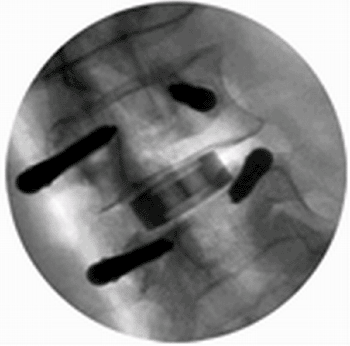

Advanced Visualization System Aids Spinal Surgery